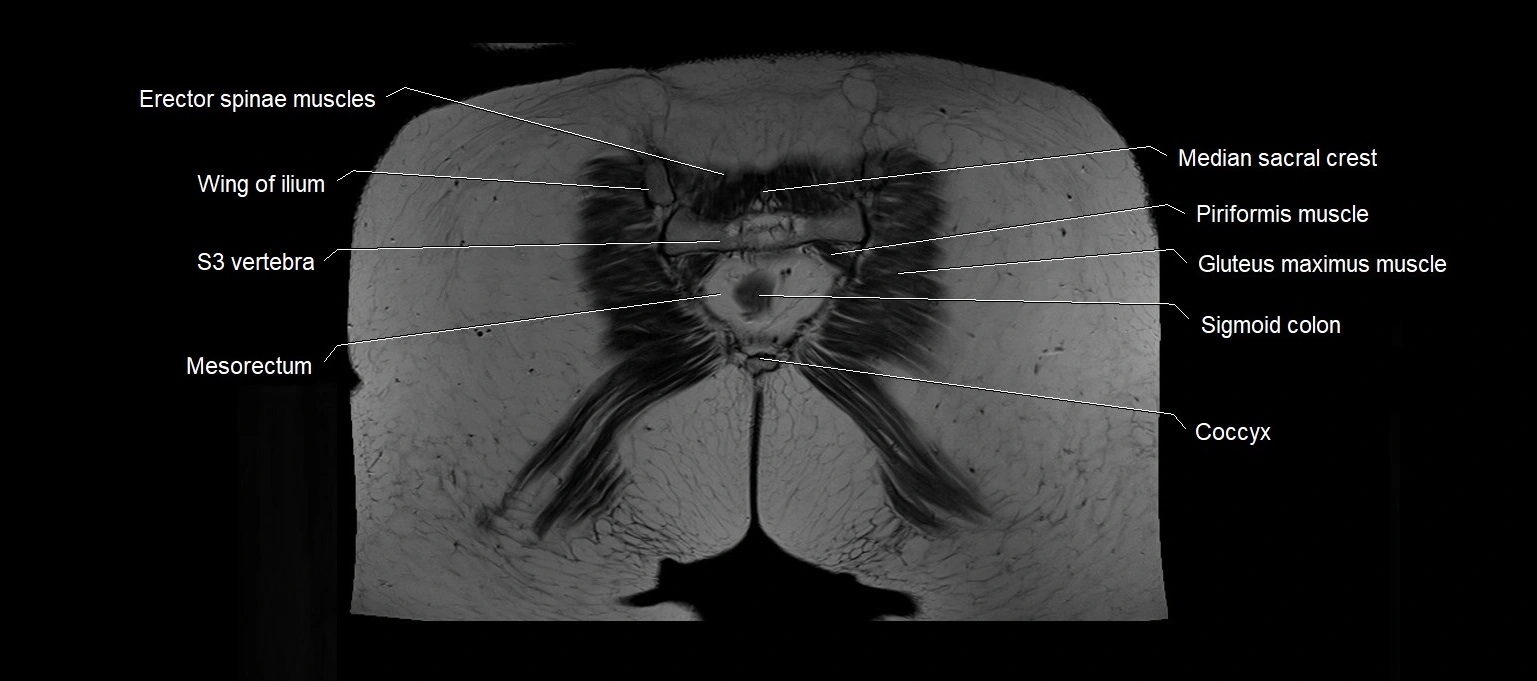

MRI images